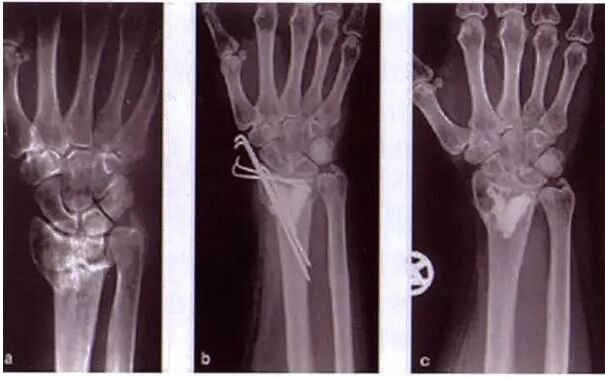

骨粉早年常用于鞍鼻的注射,主要应用于鼻根及鼻背部凹陷的矫正,但不能用于鼻尖塑形,因为鼻尖部是软骨构成,使用羟基憐灰石填充,会导致鼻尖过硬,形状与手感皆不自然。

由于骨粉是不可吸收的性填充剂,在注射后很快就会与鼻骨融合,并会一定程度诱导不可调控的骨性增生现象,导致后期形态的改变,—旦效果不满意,必须通过手术刮除,且很难彻底取净,手术过程本身可能比骨粉的存在有着更大的风险。

因外形不佳,变宽、变形等,患者要求取出,只得使用外科手术方法,明视下操作,创伤极大,常常要使用刮匙或骨锉,不仅不能取净,还有损伤其他正常组织的可能,导致皮肤变薄或组织坏死,后期二次修复时,可能还要再移植或筋膜修复,极其复杂。